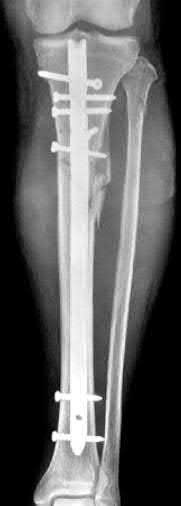

A 28-year-old male sustains a closed comminuted tibial shaft fracture.

Two hours post-injury, he develops severe leg pain unyielding to narcotics. His blood pressure is 120/80 mmHg. Intracompartmental pressure monitoring is performed. Based on current guidelines, which measurement dictates an emergent 4-compartment fasciotomy?

Explanation

Acute compartment syndrome is classically defined by tissue hypoperfusion. The absolute compartment pressure is less reliable than the differential pressure (Delta P). A Delta P (Diastolic Blood Pressure minus Compartment Pressure) of less than 30 mmHg is an absolute indication for emergency fasciotomy, as capillary perfusion gradient is lost when tissue pressure approaches the diastolic pressure.